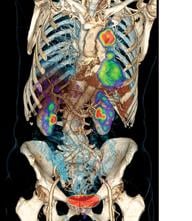

The variety of radiation therapy options continues to grow with the development of treatment planning software, imaging systems for guidance, linear accelerators and more. The external-beam radiation therapy (EBRT) market includes many different types of treatment, from traditional whole-body irradiation (WBI) to conformal radiation therapy (3-D CRT) and intensity-modulated radiation therapy (IMRT). Despite a major decline in 2009, the U.S. radiation therapy market is bouncing back, according to a study published in July by IMV Medical Information Division.[1] Improvements in technologies are helping to drive activity as clinics and hospitals implement advanced techniques to more accurately target and treat cancers.